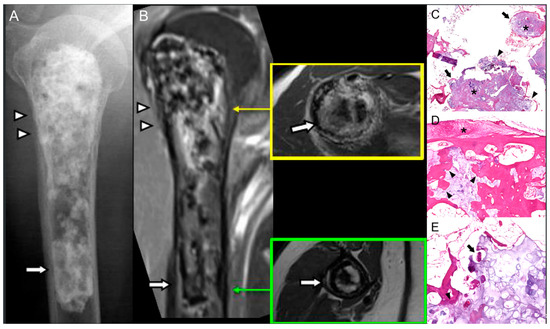

Malignant Transformation of Musculoskeletal Lesions with Imaging–Pathology Correlation—Part 1: Bone Lesions

by Hyang Sook Jeong, Seul Ki Lee, Jee-Young Kim, Changyoung Yoo and Min Wook Joo

Background/Objectives: Malignant transformation of bone lesions, although rare, poses a major diagnostic and clinical challenge. Common benign lesions (e.g., osteochondroma, enchondroma, fibrous dysplasia, giant cell tumor), non-tumorous conditions (e.g., chronic osteomyelitis, irradiated bone, infarction), and low-grade malignancies (e.g., low-grade osteosarcoma, chondrosarcoma) can evolve [...] Read more.

Background/Objectives: Malignant transformation of bone lesions, although rare, poses a major diagnostic and clinical challenge. Common benign lesions (e.g., osteochondroma, enchondroma, fibrous dysplasia, giant cell tumor), non-tumorous conditions (e.g., chronic osteomyelitis, irradiated bone, infarction), and low-grade malignancies (e.g., low-grade osteosarcoma, chondrosarcoma) can evolve into aggressive malignancies through distinct genetic, molecular, and microenvironmental pathways. Recognizing early malignant transformation on imaging is crucial for timely diagnosis and management. Methods: This review synthesizes current imaging characteristics, pathologic mechanisms, and clinical risk factors associated with malignant transformation of benign and low-grade malignancy bone lesions. Results: Atypical imaging findings and inaccurate biopsies can delay diagnosis. Aggressive features—such as cortical destruction, heterogeneous enhancement, and loss of internal matrix—should prompt further pathologic evaluation. Advanced imaging and a multidisciplinary approach with integrated clinicoradiologic–pathologic review are essential to minimize missed diagnoses. Patients with risk factors such as genetic syndromes, prior denosumab therapy, inadequate surgery, or prior radiation therapy require close monitoring or timely intervention. Conclusions: Radiologic–pathologic correlation remains central to distinguishing benign from malignant lesions. This review article emphasizes a comprehensive imaging-pathology overview of benign and low-grade malignancy bone lesions with malignant potential, aiming to improve diagnostic accuracy and outcomes in orthopedic oncology. Full article